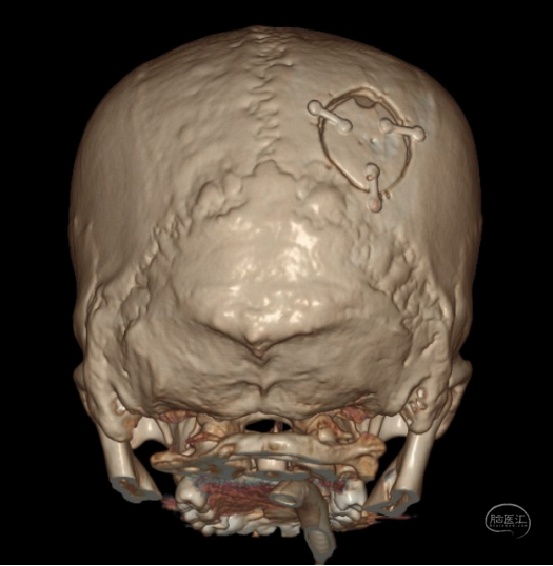

穿刺位置:枕骨粗隆上8.5cm,中线旁开3.5cm

切口:“S”型切口,避开枕动脉主干

骨窗